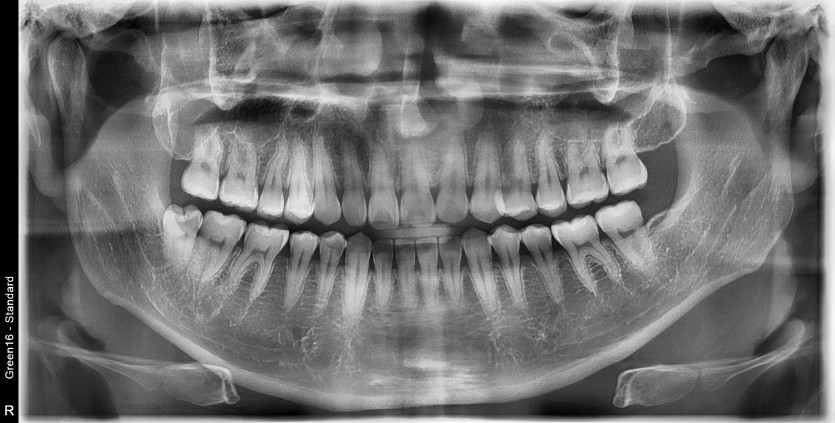

#48 사랑니 발치

구강 외과 전문의가 당일 발치했습니다.